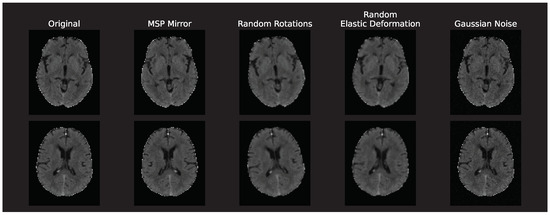

Appendix B. NCCT Augmentations